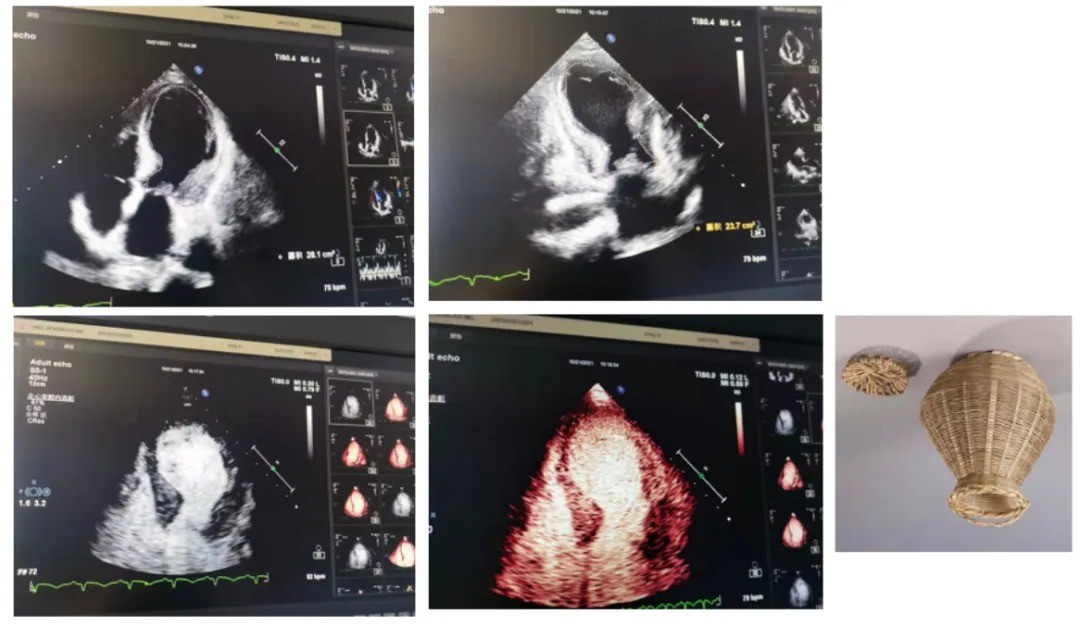

「考虑应激性心肌病!射血分数 32%。」小颖眼睛都亮了,我心中一动,研究生时候我见过一例的,就是那个「心碎综合征」?

患者超声心动图,右图为日本捕章鱼的罐子

图源:天津医科大学总医院超声心动室 杜鑫主任提供